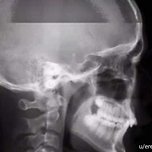

어째 하루만에 이렇게 되나... ㅜㅜ 병원 갔더니 코점막이 다 터졌다고 ㅠㅠㅠㅠㅠ 모르는 내가 봐도 붓고 울퉁불퉁 하덥디다..